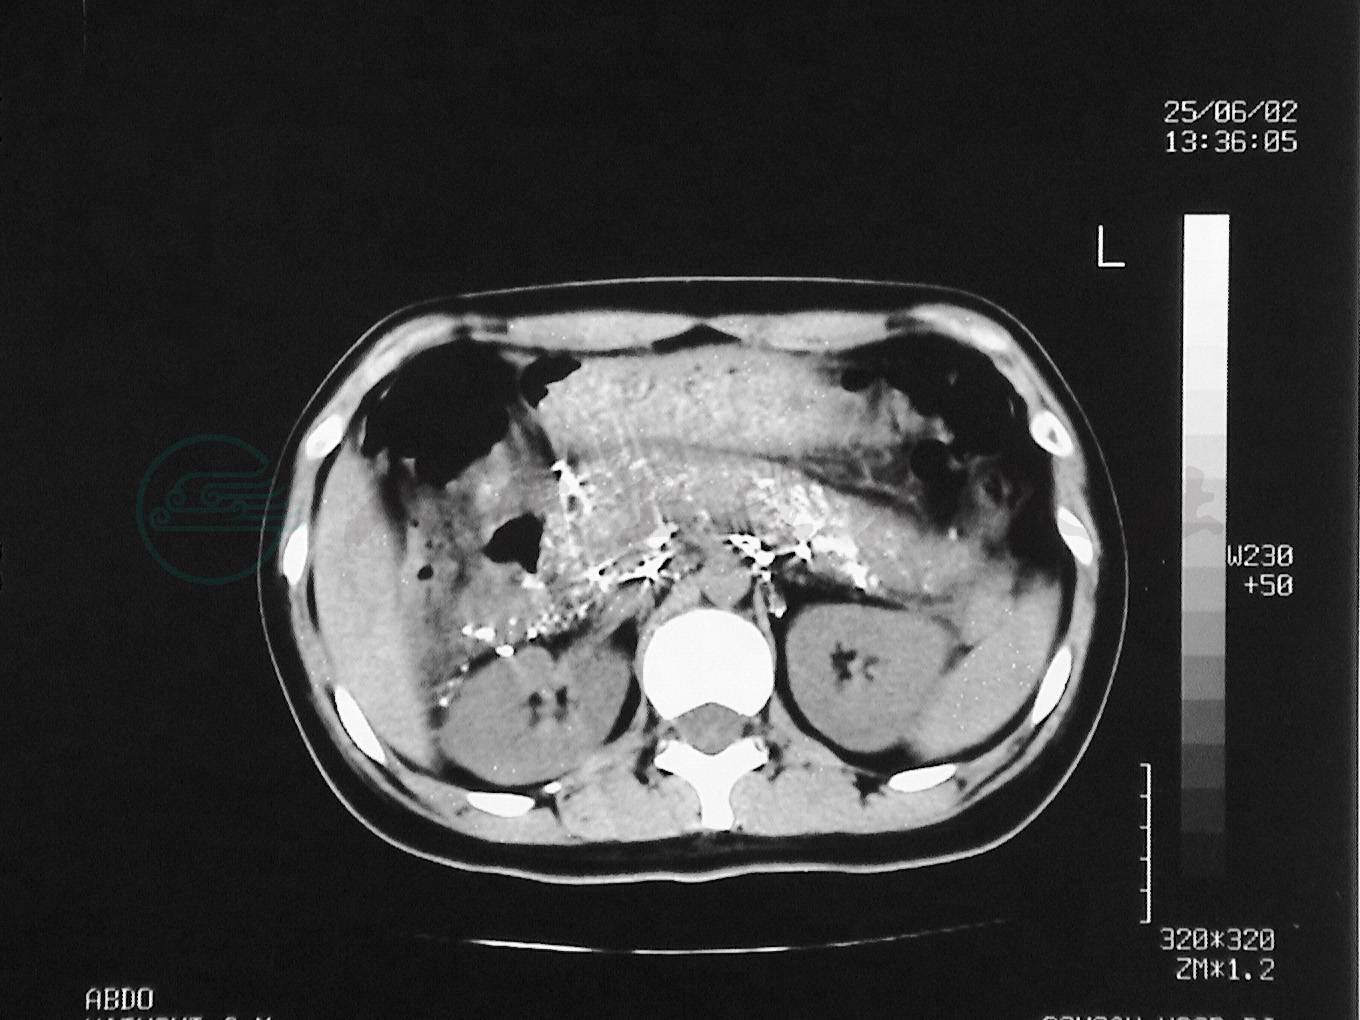

5.直接淋巴管造影后的CT影像

对淋巴管疾病直接淋巴管造影后的患者,选择性做CT检查(简称淋巴管增强CT,lymphatic contrast computed tomography,LCT)以进一步探讨淋巴管疾病的诊断、认识淋巴管疾病的病理生理过程。

普通CT影像对淋巴管结构难以有阳性发现。LCT影像,能精细地显示造影剂分布状况,清楚地显示造影剂与周围脏器的关系,在直接淋巴管造影基础上,能更全面地了解淋巴管病变范围与准确部位,能发现淋巴管造影的资料遗漏,对乳糜回流障碍的诊断,以及对手术方式的选择,尤其是对要结扎的淋巴管或要切除肿物的准确定位,有重要作用,还能发现骨骼淋巴管病变、碘油进入骨骼结构等。因此,在直接淋巴管造影不能做出判断时,可选择行LCT检查。但因其影像是平面的,不能准确提供造影剂与周围组织脏器的关系,因人为选择摄片区域和时间,可能造成影像资料无意丢失。